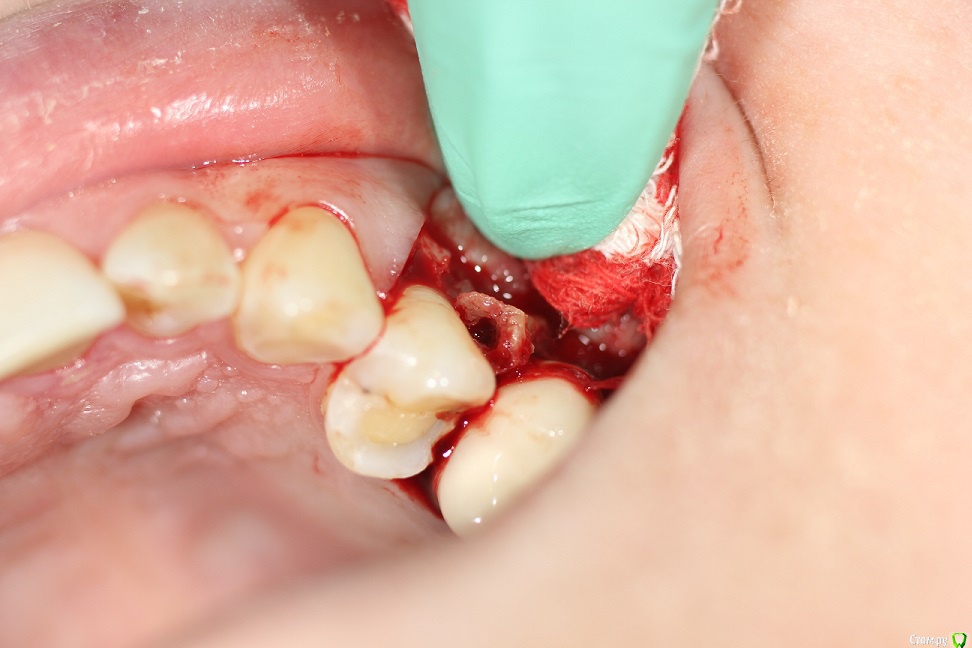

kuziy12 Опубликовано 8 марта, 2020 Автор Поделиться Опубликовано 8 марта, 2020 Как то так. Попытался вообще без откидывания, но тогда бы секвестр десну порвал, большой слишком. Уже его чуть сдвинул:Убрал грануляции:Ушился:Это секвестр: 3 Ссылка на комментарий